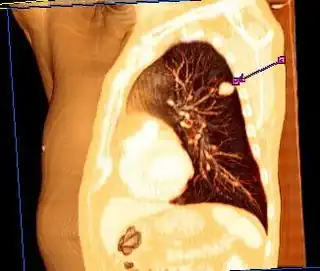

Corte torácico en un estudio tomográfico mostrando la localización de un tumor de cáncer pulmonar.

Tomografía axial computarizada

Imagen de una tomografía que muestra un tumor canceroso en el pulmón izquierdo (flecha).

La tomografía axial computarizada es de gran utilidad en el cáncer de pulmón y se recomienda en todo paciente con un nódulo pulmonar solitario detectado por radiografía.[121]​ Algunas ventajas de una tomografía incluyen:

• Encuentra su principal aplicación en la determinación del grado de extensión de la neoplasia; tanto intratorácica como extratorácica, y de las adenopatías mediastínicas.[134]

• En la diferenciación entre nódulos benignos y malignos, además de la detección de pequeños nódulos con mayor nitidez que en las radiografías simples. Proporcionan valiosa información sobre la existencia de cavitación, calcificación y en ocasiones la localización intrabronquial del tumor, en fin, de las características morfológicas del tumor.

La tomografía es un método muy demostrativo de la afectación mediastínica del carcinoma de pulmón, de la evaluación de los ganglios retroperitoneales, crurales, así como del estado del hígado, suprarrenales y riñón, frecuentemente afectados por metástasis. Permite además el análisis de lesiones subpleurales y la visualización de pequeños derrames, la posible afectación de pared —ya que permite una correcta visualización de la pared costal— y la visualización de la extensión del tumor a otras estructuras colindantes.